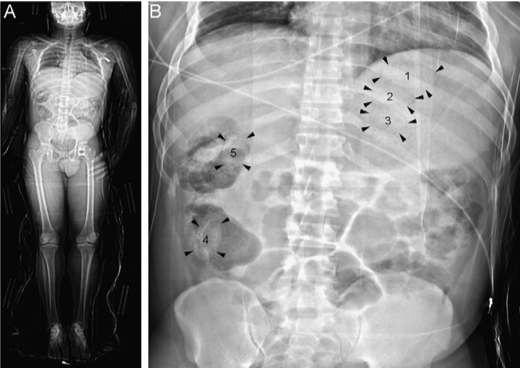

Klinik Görüntüler

Yukarıdaki örnek görüntüler, Lodox Xmplar-dr sisteminin her yaş ve vücut tipindeki hastalarda sunduğu yüksek çözünürlüklü tam vücut görüntüleme kapasitesini göstermektedir. Pediatrik hastalardan erişkinlere, düşük kilolu bireylerden yüksek vücut kitle indeksine sahip hastalara kadar geniş bir hasta grubunda net anatomik detay elde edilebilmektedir. Linear slot-scanning teknolojisi sayesinde kemik, yumuşak doku ve yabancı cisimler tek çekimde, ortalama 13–16 saniyede ve ultra düşük radyasyon dozu ile görüntülenir. Bu özellik, özellikle travma ve acil servis koşullarında hem hızlı tanı koymayı hem de radyasyona bağlı riskleri en aza indirmeyi mümkün kılar.